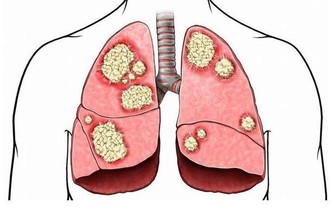

骨質疏鬆症的主要特徵是骨礦物質含量低下、骨強度降低、易發生骨折等。上了年紀的老人家走路駝背、身高降低,其實都是骨質疏鬆症的表現。

與此同時,骨質疏鬆症也被稱為“沉默的殺手”。因骨頭“變脆”,容易導致骨折。